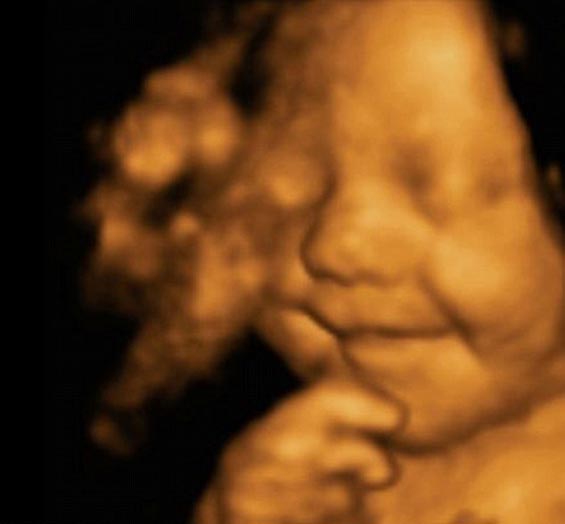

هذه الصورة مأخوذة من بجهاز الموجات فوق الصوتية رباعية الأبعاد "الألتراساوند" في الأسبوع الـ31 من عمر الجنين، والآن يبلغ الطفل الذي سُمى بـ"ليو هارغريفس" من العمر 5 شهور، ويتسم بضحكته البشوشة ووجهه الضاحك المبتسم دائماً والذي بدأ ابتسامته البريئة منذ قبل ولادته.

وقالت والدته إيمي كريغ (24 عاماً) إن طفلها لم يتوقف عن الابتسام والضحك منذ ولادته، فهو مبتسم دائماً، حتى أثناء نومه، لدرجة أن شركة دعاية وإعلان قررت التعاقد مع الأسرة بغرض الاستفادة من صور ليو المبتسمة دائماً، بحسب ما ورد في موقع دايلي ميل البريطاني.